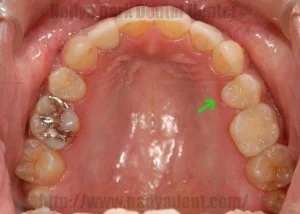

Before

After

古い金属の詰め物をすべて除去し、セラミック等の白い材料でやりかえた事例

噛み合わせの調整後、金属除去、型採り、装着のステップで実施 / セラミック1本 ¥80,000~(税別) + 型取り ¥3,000(税別) (※本症例では右下6・左下6にセラミック、右下7・左下7に保険内CR、その他小金属に保険内修復を適用)リスク・副作用:治療後に一時的なしみや違和感が生じる可能性。過度な衝撃による破損や、経年劣化による変色・脱離のリスク。